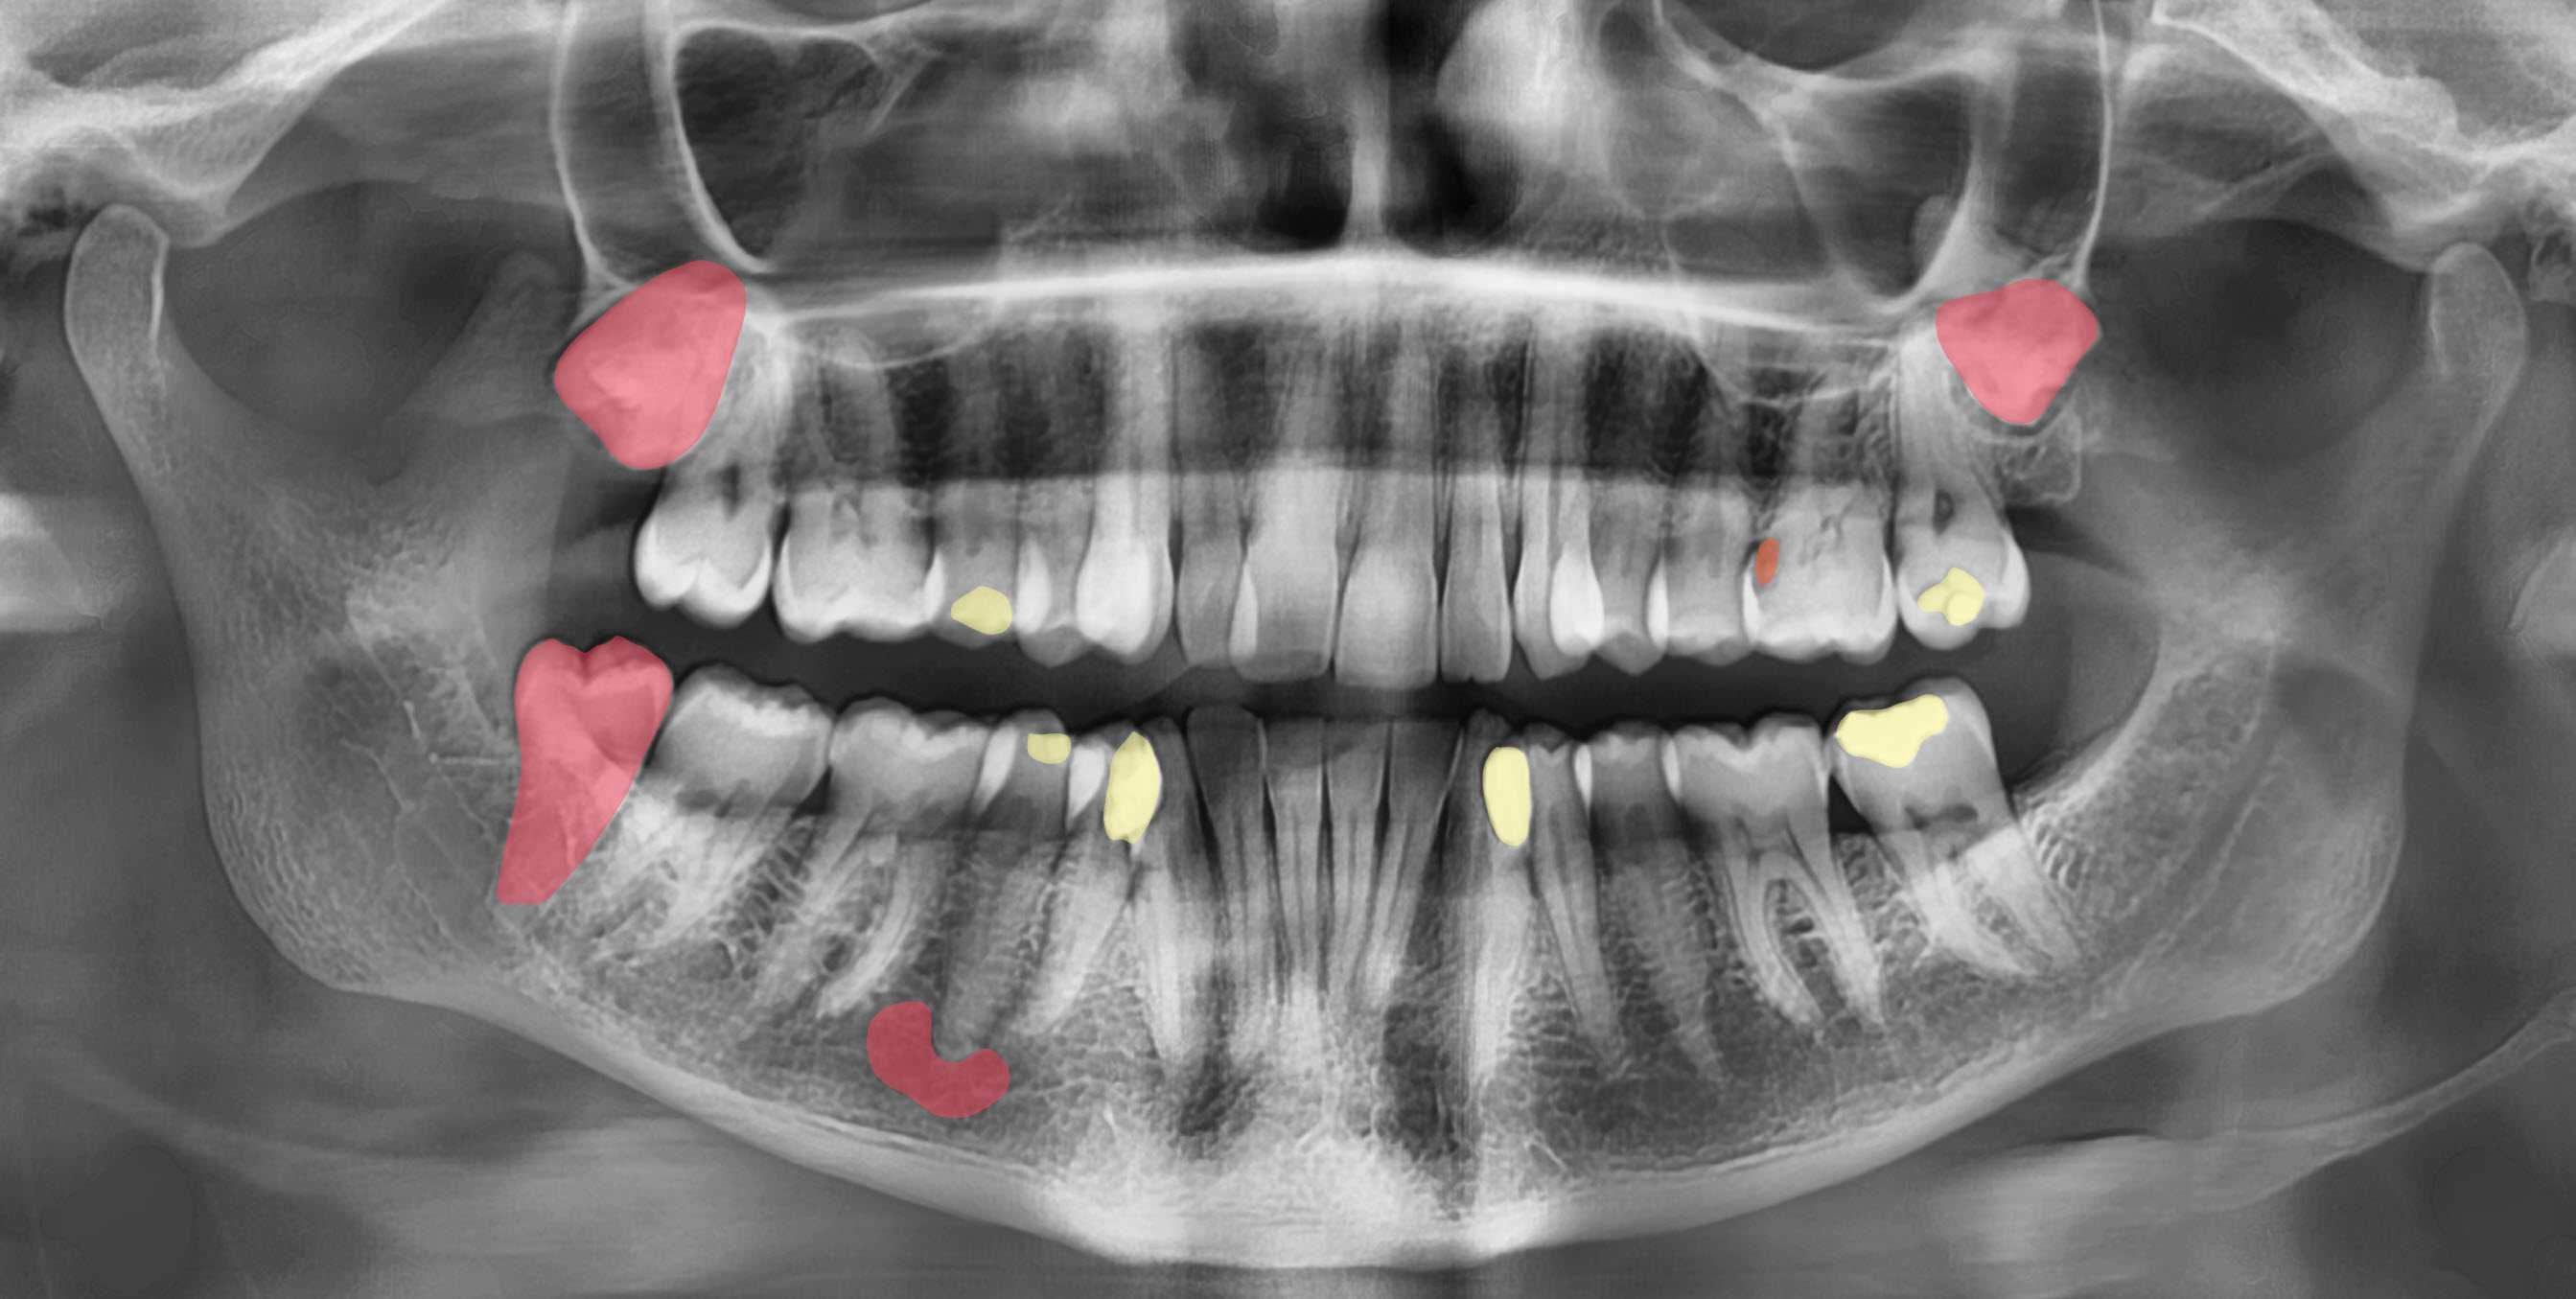

Diagnoplan is specialized in providing digital dentistry online services, including reporting, designing, and planning. Starting from diagnostic reporting , planning, and AI services till designing a final appliance. We use the latest technology and advanced software to design precise appliances tailored to your patient, including surgical guides, PSIs, orthognathic wafers and many more.